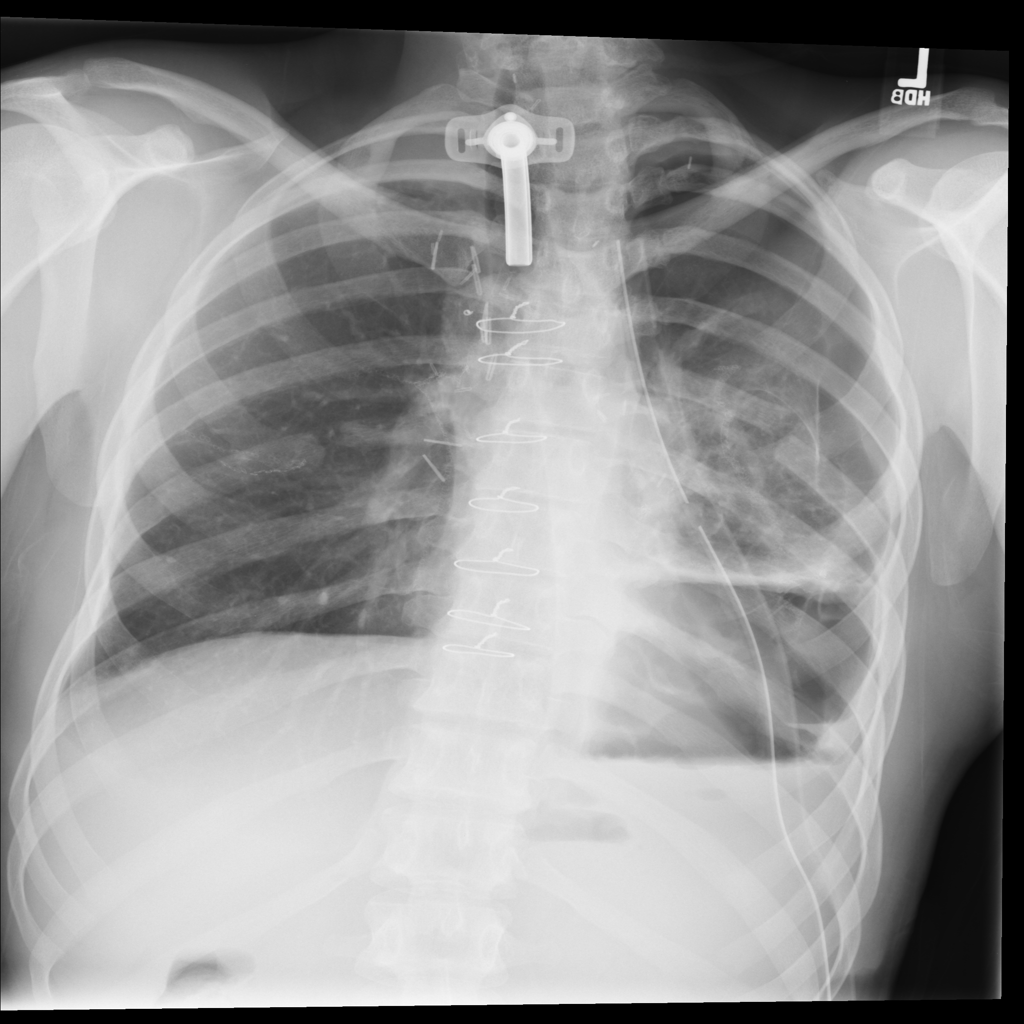

PAT-4639 · IMG-011Pneumothorax

PAT-4639 · IMG-011

AP